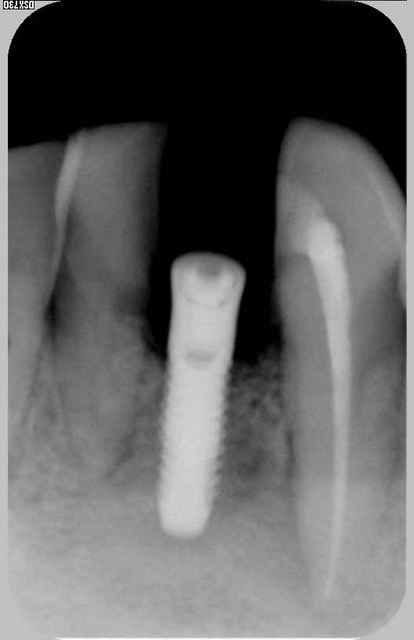

début en 2001 : patient avec perte de 32 me demande de remplacer dent manquante réponse ok avec pano et rvg pas de scan vu la hauteur visible et en pus on est en 32 .

le jour de la pose : j'avais prévu un 12*3.3 je le mets en place mais tourne à15 newton donc poubelle et je mets en pace 4*12 blocage à 30 newton mais sensation particukière au forage

puis attente et au deserrage de la vis je dévisse sans effort ce 4*12 la nje fait 1 scan qui confirme qu'iln'y a rien dans le "sandwich" bicortical qui est bien présent donc endo de 33 depose en deserrant la vis de l'implant sans effort curetage ++++ pas de prf et perlimpinpin attente de cicat 6 mois

et repose d'1 3.3*12 (on en est à 3 futs) attente bonne sensation au forage et attente avec atelle collée toujours puis 6 mois après en serrant le fm

à 30 le patient me dit "il y à qqchose de sensible" je mets la provisoire quand même qui est restée en place 1 an et demi mais je l'ai déposé (mobilité +++) et ai réalisé une prothèse "conventionelle"

2)sur la densité si on regarde la rétro a postériori idem pour la pano on devine très bien ce pb de densité (surtout quand on le sait cliniquement)